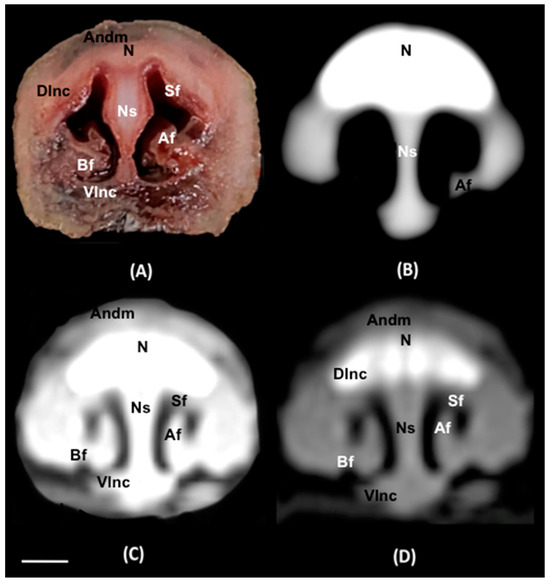

Abstract

3. Results

3.1. Anatomical Sections